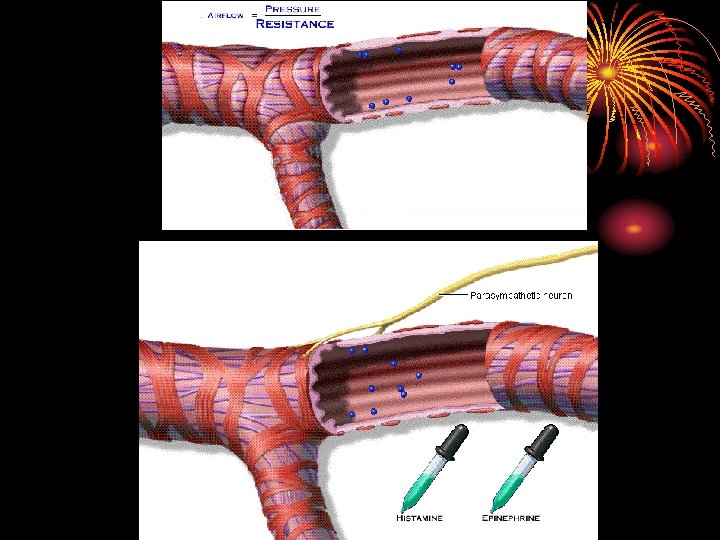

Bronchial tone • Bronchioles have no cartilage and more smooth muscles. • Bonchio. dilate during inspiration by sympathetic discharge. B 2 receptors. salbutamol. • Broichio. constrict during expiration by parasympathetic- muscaranic receptors. ipratropium.